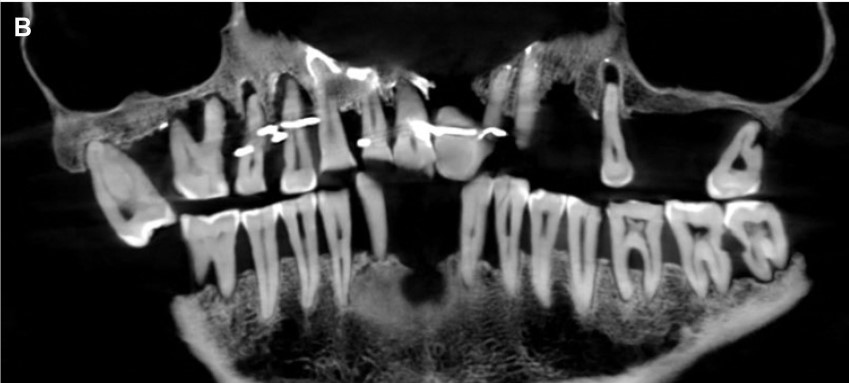

A handout picture released by the French National Institute of Archaeological Researchs (Inrap) on January 25, 2023 shows a close up in picture and in radiograph of the skull of Anne d'Alegre, a 17th-century aristocrat. (Photo by Handout / INRAP / AFP)

A close-up in picture and in radiograph of the skull of Anne d'Alegre. (Photo by Handout / INRAP / AFP)

A "Cone Beam" scan, which uses X-rays to build three-dimensional images, showed that gold wire had been used to hold together and tighten several of her teeth.